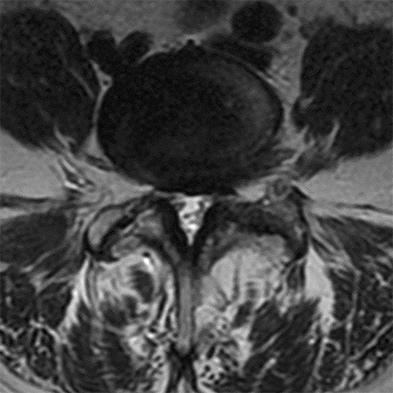

Figures 1 and 2 show sagittal and axial MRI from an 83-year-old woman with an ataxic gait, loss of dexterity, and intermittent loss of bowel and bladder control. The symptoms have been getting progressively worse over the past several weeks.

What disease process is most likely the cause of the patient’s symptoms?

4. Pigmented villonodular synovitis Discussion: B

The patient has a pannus at the C1-2 articulation that is compressing the spinal cord and causing myelopathy symptoms. The development of a pannus at this location has been associated with rheumatoid arthritis. Steinberger and associates showed increased morbidity and mortality when using an anterior approach and the surgery took longer than 4 hours. Chieng and associates showed better outcomes and lower complications rates using a posterior approach.